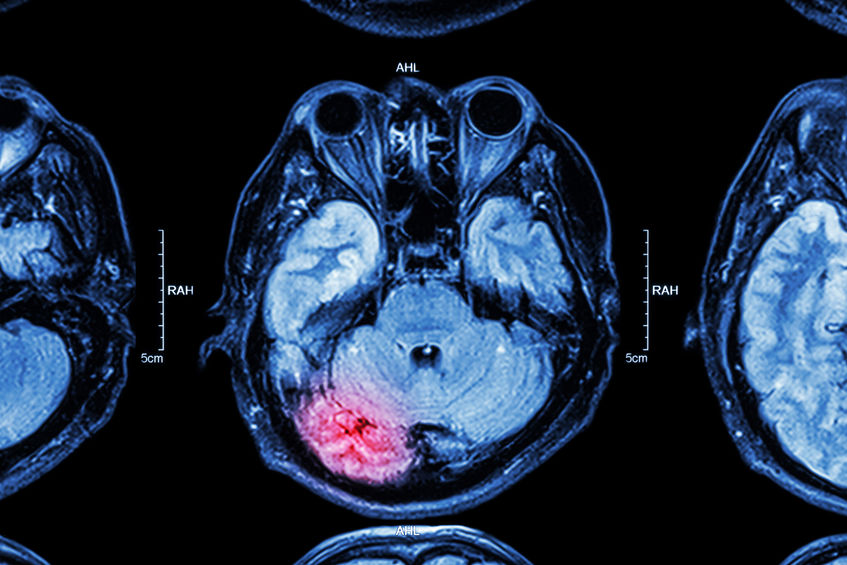

As doenças neurológicas estão ligadas ao prejuízo do cérebro, dos nervos periféricos ou da medula espinhal, que compõem o sistema nervoso central e o periférico.